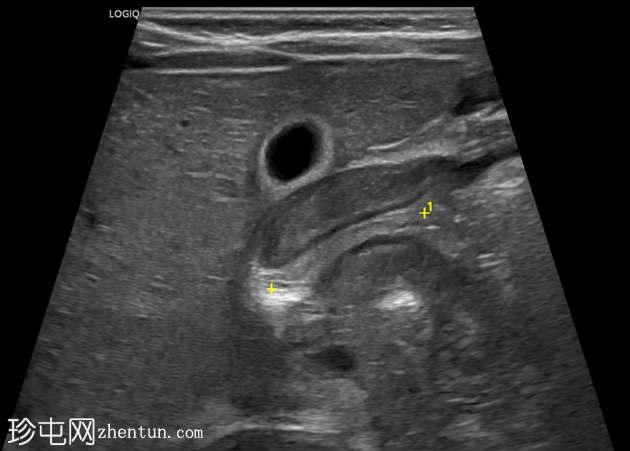

超声

检查

斜位

幽门管明显增厚,测量结果如下:

单层肌肉厚度约5毫米

管径约15毫米

管长约20毫米

横位图像显示幽门管狭窄的靶征。

总体测量结果提示肥厚性幽门狭窄。